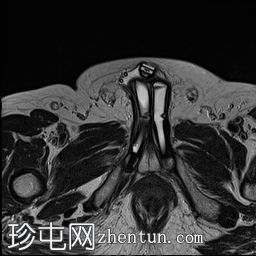

轴位

T2加权像

MRI显示可充气式阴茎假体位于体内。

假体柱体对称地位于阴茎海绵体内,并沿其走行方向完全扩张。

未见海绵体破裂或假体柱体断裂的迹象。

泵储液囊位于阴囊内,位置正常。

阴囊壁皮下可见轻度水肿,但无明显积液,可能为反应性水肿。

储液囊位于右侧腹股沟管前方的皮下脂肪内,对右侧腹直肌施加轻微的向上压迫,周围有少量积液。这些发现最符合术后改变。

在本病例中,MRI显示假体圆柱体位置正常,无破裂或不连续的迹象。储液囊和泵的位置也正确。周围轻微的水肿和积液可能是术后改变。因此,患者的症状可能与机械刺激或装置相关的机械因素有关,而不是假体的结构性故障。